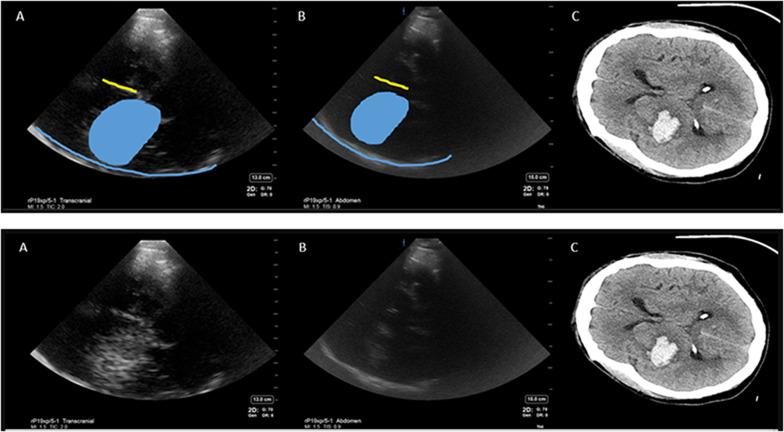

After obtaining IRB approval, a blinded investigator performed cranial ultrasound (Fujifilm, Sonosite Xporte, transcranial and abdominal presets) through temporal windows on 11 patients with intracerebral pathology within 72 h of last CT/MRI (computed tomography scan/magnetic resonance imaging) brain after being admitted to a neurocritical care unit in Aug 2020 and Nov 2020-Mar 2021. Images were then compared to patient's CT/MRI to inform topography. Inferential statistics were reported.

Mean age was 57 (28-77 years) and 6/11 were female. Six patients were diagnosed with ICH, 3 with ischemic stroke, 1 subarachnoid hemorrhage, and 1 brain tumor. The sensitivity and specificity of point of care diagnosis of ICH compared to CT/MRI brain was 100% and 50%, respectively. Mean time between ultrasound scan and CT/MRI was 13.3 h (21 min-39 h). Falx cerebri, choroid calcification and midbrain-related artifacts were the most reproducible hyperechoic signals. Abdominal preset on high gain yielded less artifact than Transcranial Doppler preset for cranial B mode imaging. False positive ICH diagnosis was attributed to intracerebral tumor and midbrain-related artifact.

平均年龄为57岁(28 - 77岁),11例中有6例为女性。6例患者被诊断为ICH,3例为缺血性卒中,1例为蛛网膜下腔出血,1例为脑肿瘤。与头颅CT/MRI相比,POCUS诊断ICH的敏感性和特异性分别为100%和50%。超声扫描与CT/MRI之间的平均时间为13.3小时(21分钟 - 39小时)。大脑镰、脉络丛钙化和中脑相关伪像是最可重复的高回声信号。对于头颅B模式成像,腹部预设在高增益时产生的伪像比经颅多普勒预设少。ICH诊断的假阳性归因于脑肿瘤和中脑相关伪像。